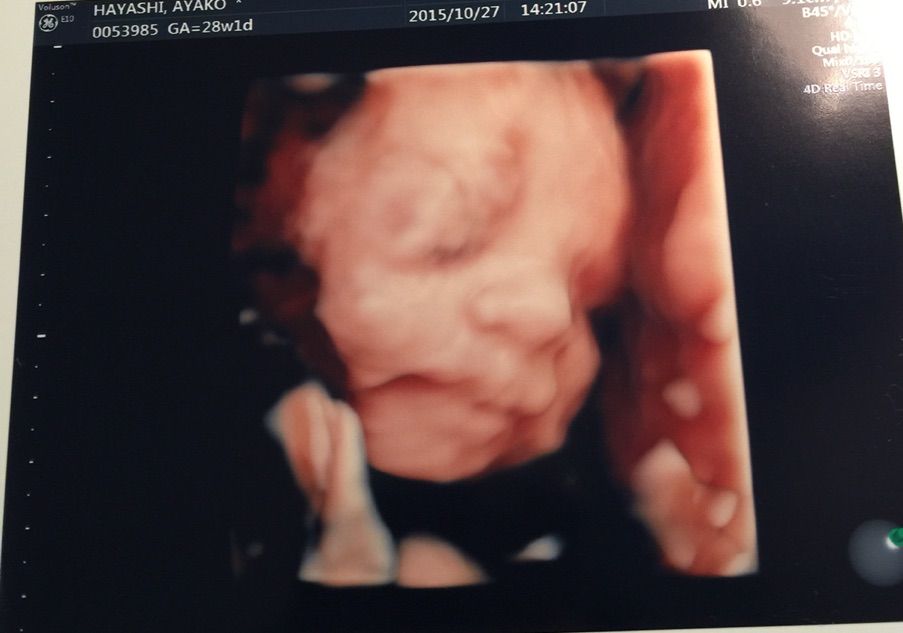

…って事で、昨日は撮影後に4Dエコーなるものを見る為に妻と病院へ。

タイミング次第では、全く顔が見えない事もあるそうで我が子の顔が見れるのか?少しドキドキしてたんですが…

無事?ご対面出来ました(^ ^)

結構動いてたので手足が邪魔して見えなくなったりしましたが…

手も足も元気な証拠かな?とか思いつつ、右手の指がなんとなく5本確認できたのでハサミは握れるな!とかも密かに思ったりしてました( ^ω^ )

最後には、ニッコリ笑ってくれた…様な気がしましたが…えぇ、既に親バカですσ(^_^;)

初め見た時は、ヴォルデモート感がスゲェな…とか思いましたが、後半は不思議と可愛く思えてきましたもんね( ^ω^ )

少しずつではありますが、我が娘がそこに居てその娘の親になるんだなぁ…と実感する機会が増えてきました。